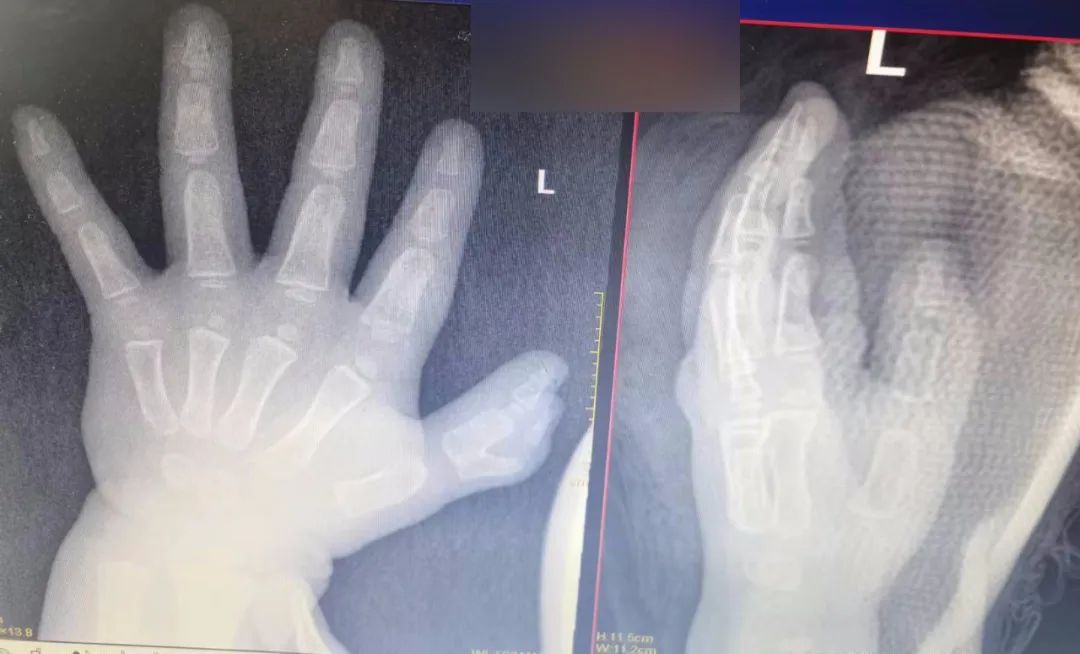

琪琪(化名)今年 1 岁,是一个手指天生畸形的患儿,她的左手和普通人不一样,长了两个黏连的大拇指,看着像个「小蟹钳」,外观怪异,功能也受到影响。

手足外科医生为琪琪安排相关检查,发现琪琪的大拇指犹如「螃蟹钳」,手术会涉及到截骨、关节囊的重建和肌腱的重构等,手术难度加大。为确保手术优质实施,手足外科团队进行详尽的讨论,最终制定了完善的手术策略及方案——「左拇指多指畸形切除术+关节囊修复术+伸指功能重建术+石膏固定术」。